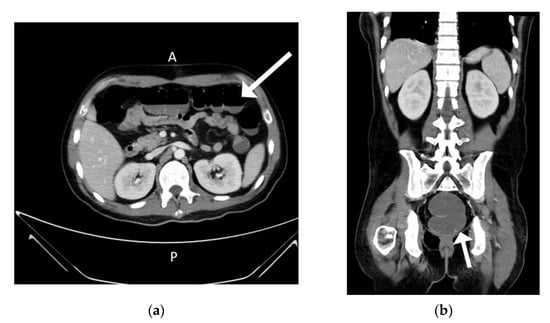

The patient’s spiking fever and polyarthritis subsided after the VATs tumor resection. The methylprednisolone dosage was tapered gradually from 40 mg/day to avoid adrenal insufficiency. However, the high fever returned 5 days after the operation and did not respond to antibiotics. Cytomegalovirus (CMV) viremia developed with a serum viral load of 5418 copies/mL, and ganciclovir was prescribed. Ileus and intermittent hematochezia developed gradually 8 days after the VATs (Figure 6).

Figure 6. Ileus and hematochezia after 8 days of tumor resection. (a) Air-fluid level over transverse colon region (b) Sigmoid colon dilation.